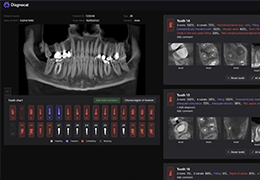

分析智能。

这些功能利用数字控制面板分析运营、业务和临床绩效。

使管理员能够跟踪关键参数,包括平均曝光率、拒绝的影像和探测器统计信息。

帮助确定需要改进的方面,支持为员工和部门制定适当的改进计划。